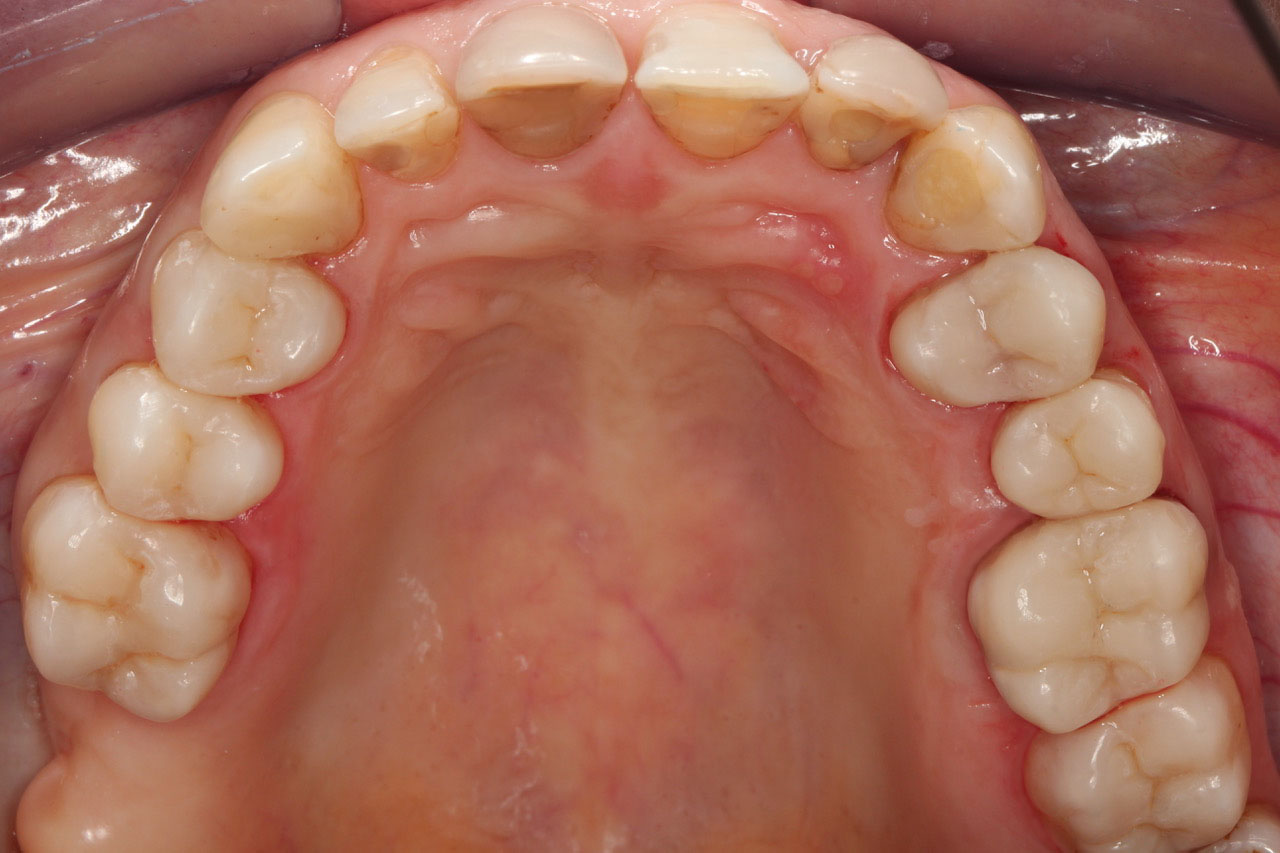

4. Nakłady (plomby) kompozytowe w zębach bocznych

wykonane w laboratorium